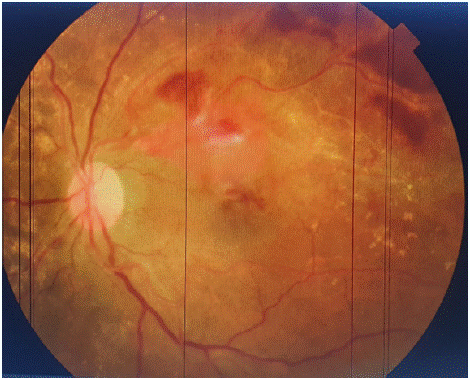

On clinical examination, her vision was severely reduced in the LE to hand motion only; she had preserved vision in the right eye (RE) to 10/10. Both eyes had relatively normal anterior segments and intraocular pressure. Fundus exam revealed multiple yellowishwhite flecks, predominantly pisciform but with a few round ones, distributed in the macular region (Figure 1). There were signs of arteriovenous crossing and there was also dense retrohyaloid and subretinal hemorrhage, covering the entire macular area in the LE (Figure 2).

Figure 1: Fundus right eye: multiple yellowish-white flecks, predominantly

pisciform but with a few round ones, distributed in the macular region.